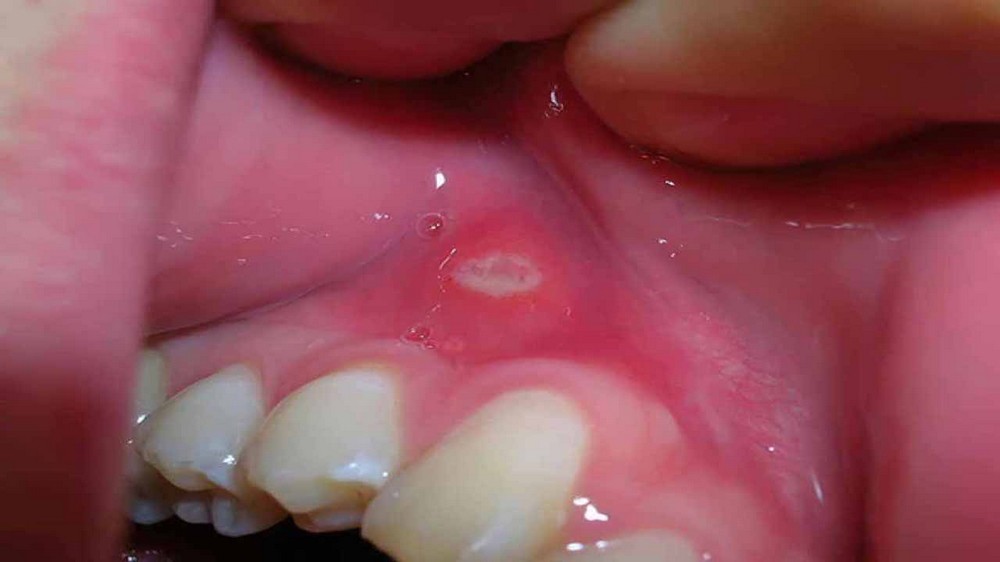

Bệnh nhiệt miệng là một hiện tượng “loét miệng” phổ biến, màu sắc của các vết loét thường là hồng nhạt, gây ra cảm giác đau rát và khó chịu khi ăn uống và vệ sinh răng miệng.

Nhiệt miệng có thể xuất hiện các mụn nước ở trong má, vòm họng và niêm mạc miệng, gây ra cảm giác khó chịu và đau nhức khi vô tình cắn trúng, đánh răng hoặc thức ăn đụng vào.

Tình trạng chảy máu khi bị nhiệt miệng có thể do những mụn nước này chứa máu, khi vỡ thì máu sẽ chảy ra. Tuy nhiên, tình trạng này cũng khá hiếm xảy ra và thường là biến chứng của bệnh nhiệt miệng trở nên nặng hơn. Điều này cũng có thể gây nhầm lẫn với bệnh ung thư khoang miệng.

Tuy nhiên, các chuyên gia cũng nêu rõ sự khác biệt rõ ràng giữa hai tình trạng này. Hiện tượng chảy máu do mụn nước vỡ chỉ kéo dài từ khoảng 7-10 ngày, trong khi bệnh ung thư khoang miệng có thể kéo dài hơn 15 ngày. Điều này cũng cho thấy màu sắc trong niêm mạc miệng thay đổi, trở nên đậm hơn.